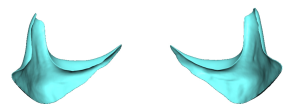

Custom (patient-specific) implants:

- Are designed from CT scan data

- Precisely match orbital rim curvature and asymmetry

- Can extend into multiple regions, including:

- Infraorbital rim

- Pyriform aperture

- Maxilla

- Allow controlled forward projection where needed

Implant Design Components (Single Integrated Piece)

1. Infraorbital Rim Augmentation

- Saddles the infraorbital rim

- Adds both vertical height and horizontal projection

- Produces a superoanterior (3D) expansion of the rim

- Enhances lower eyelid support

- May be combined with soft tissue procedures (e.g., spacer grafts)

2. Medial Extension (Nasal Region)

- Extends toward the nasal bones

- Improves correction of medial tear trough deformity

- Prevents a segmented or disconnected appearance

3. Inferior Extension

- Extends below the infraorbital rim while avoiding the infraorbital nerve

- Positioned more laterally relative to the nerve

- Provides vertical support at the lid–cheek junction

- Softens the transition from a negative to a more neutral vector

4. Lateral Extension (Zygomatic Transition)

- Blends into the malar eminence

- Prevents a central over-projection or “bulge”

- Ensures a smooth transition into the lateral orbit

- May extend onto the zygomatic arch when needed for continuity

Shape and Surface Characteristics

Contouring

- Fully customized based on CT anatomy

- Accounts for asymmetry, rim depth, and globe position

Feathered Edges

- Minimize palpability and visibility

- Especially important along inferior and lateral borders

Thickness Gradient

- Maximum thickness at the infraorbital–cheek junction

- Gradual tapering medially, laterally, and inferiorly